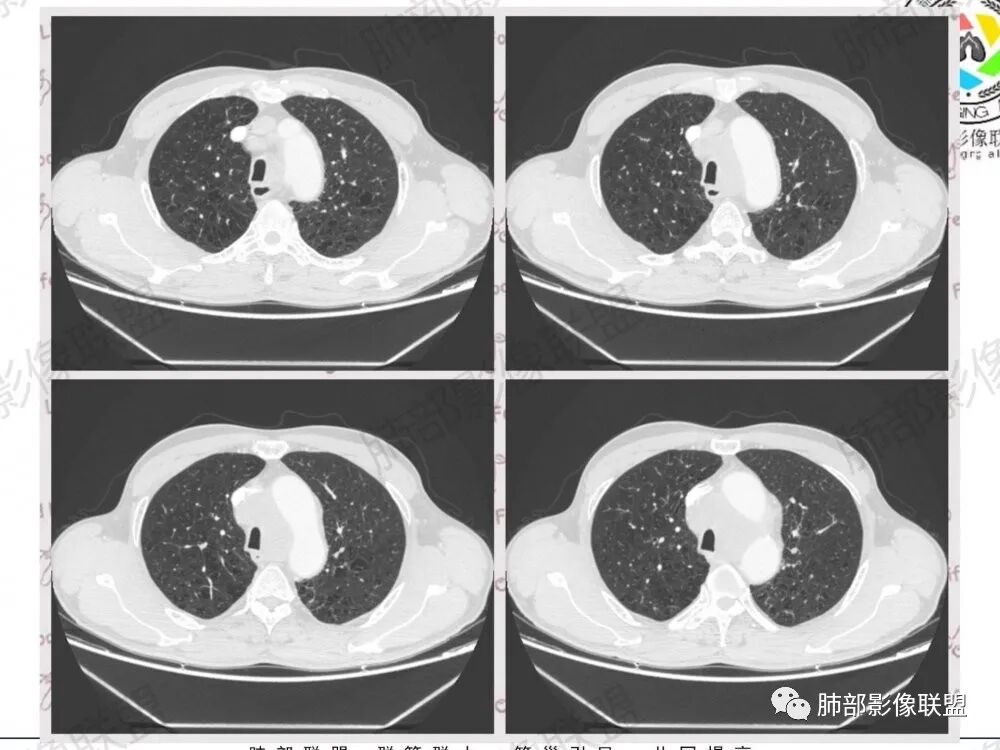

南边:纵隔淋巴结肿大病史2年,右上肺结节消失,这个病史值得玩味淋巴结肿大,中纵隔

左肺门,后纵隔

肺内好像就是慢阻肺痰栓

淋巴结有融合

病史,吸烟老年男性,这是个不好的病史问题来了,原来有左上肺结节并淋巴结肿大,治疗后好了,现在又有淋巴结肿大

小细胞癌:没针对治疗,好转,现在卷土重来,似乎不太支持,除非原来是原来,这次是新病灶,原来的病史不借鉴淋巴瘤:也一样,不借鉴病史结节病:融合,周围侵犯,不太支持原来左上肺的结节就是本次左上肺条索的位置而且右肺门不明显

1.左肺门及纵隔见异常增大淋巴结,部分融合,不均匀轻度强化,未见明显坏死。

肿大淋巴结与纵隔血管等结构“无缝”贴合。

2.纵隔增宽但依旧居中。